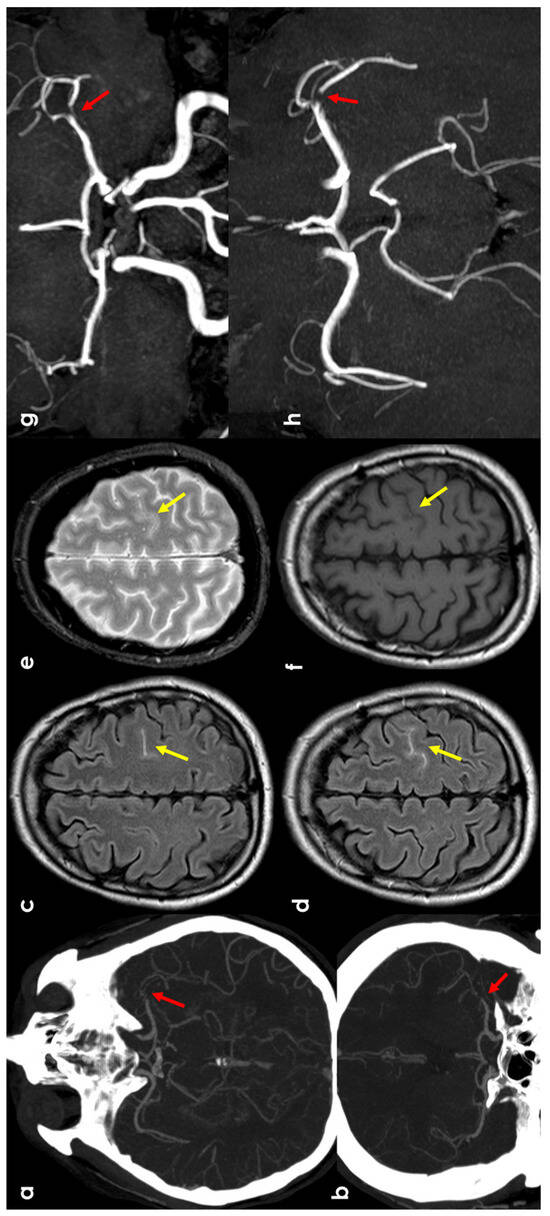

2. Epidemiology and Clinical Presentation

3.2. Hemodynamic Arterial Stenosis

3.3. Infective Endocarditis

3.4. Cerebral Venous Thrombosis